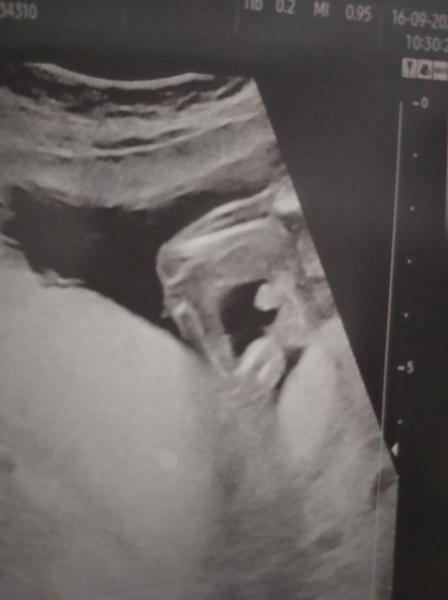

100% v medicíně nebývá obvykle nic 🙂. Podle fotky to opravdu vypadá na chlapečka, ale určitě předtím, než budete nakupovat a zařizovat, vyčkejte ještě na další ultrazvuk v 20. týdnu.